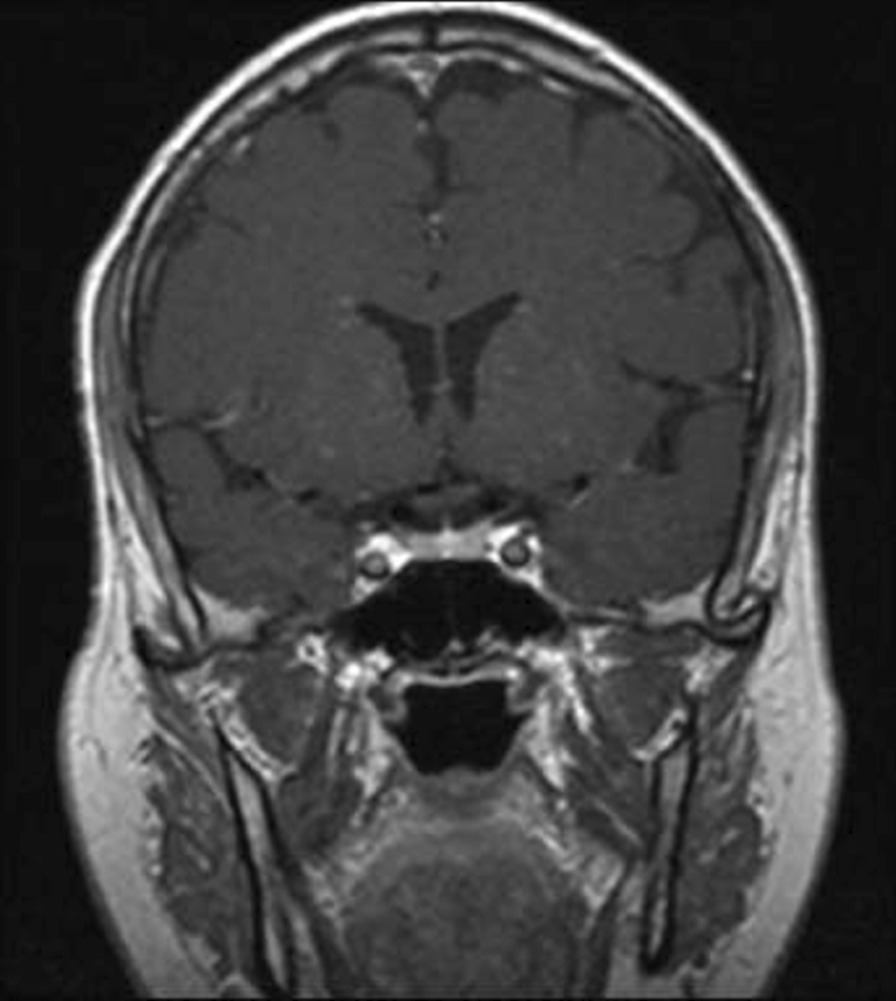

Fig. 5.

Post COVID-19 MRI findings. The image shows improvement of the pituitary microadenoma. The changes included the disappearance of the hypointense lesion and hyperintense enhancement on contrast observed on previous MRI. No macroadenoma or microadenoma is observed